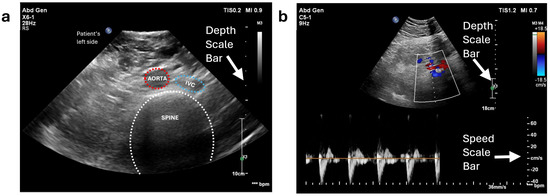

After identifying the location of the aorta or iliac artery, the next step was to determine the optimal force range required to acquire high-quality ultrasound images for each volunteer. This force range was later used during the automatic scanning process. In this step, the ultrasound probe was mounted on the robot, and the system was operated in “kinematics control” mode to vary the probe’s depth in the Z-direction. Force values and their corresponding ultrasound images were recorded across a range of forces, from 2 N (representing minimal full contact) to 10 N. The results are presented in Figure 13. For Volunteer 1 with BMI = 21, optimal image quality was observed within the force range of 3–6 N. For Volunteer 2 with BMI = 33, optimal images appeared at 4–10 N. However, to balance image quality with patient comfort, the desired force range for automatic scanning was set to 4–7 N. As the applied force increases, depth to the centre of the aorta/iliac artery decreases. This occurs because the increased force causes the abdominal tissue to deform downward, compressing and displacing any gas pockets, which brings the probe closer to the aorta/iliac artery.

Figure 13.

Ultrasound images acquired by the robot at different force levels: Volunteer 1’s abdominal aorta (yellow border) and Volunteer 2’s iliac artery (blue border). The vertical dotted line in all the ultrasound images represent a depth scale bar.